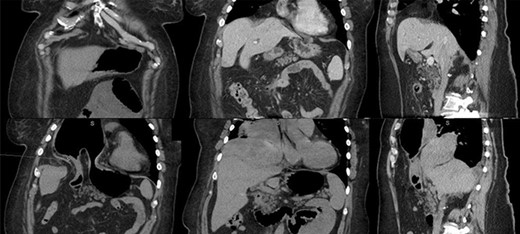

Our case involved a 72-year-old female presenting acutely with symptoms of gastric obstruction. Two months prior she had surgical treatment for a small bowel obstruction. Her management included computed tomography (CT) scan evaluation (Fig. 1, top row), diagnostic laparoscopy, lysis of adhesions and takedown of the falciform ligament. At that operation a ‘groove’ to the left of the falciform was noted and photographed (Fig. 2, top left). No repair was performed. A follow-up CT after 11 days again showed no herniation into the defect. Upon her re-presentation 2-month later with gastric obstruction, her CT showed a Morgagni hernia with an incarcerated left hepatic lobe and gastric antrum (Fig. 1, bottom row). Nasogastric decompression improved her symptoms. She was then explored using one 12 mm and two 8 mm robotic ports. She was found to have auto-reduced her stomach, but her liver required surgical reduction (Fig. 2, top right). There was no hernia sac involved in the defect (Fig. 2, bottom left). This allowed free communication between the abdomen and right chest. The defect was repaired using running 2-0 V-Loc (Medtronic, Minneapolis, MN) and interrupted 0-Ti-Cron (Medtronic, Minneapolis, MN) sutures (Fig. 2, bottom right). This was reinforced using a Parietex (Medtronic, Minneapolis, MN) coated mesh. She did well after surgery and was discharged postoperative Day 1.

Top row: prior admission imaging. Top left: anterior coronal image showing immediate retrosternal diaphragmatic defect. Top middle: posterior coronal image showing liver abutting diaphragmatic defect. Top right: sagittal image showing liver covering diaphragmatic defect. Bottom row: imaging at time of acute incarceration. Bottom left: anterior coronal image showing incarcerated gastric antrum. Bottom middle: posterior coronal image showing incarcerated left hepatic lobe. Bottom right: sagittal right paramedian cut showing incarcerated liver and stomach.